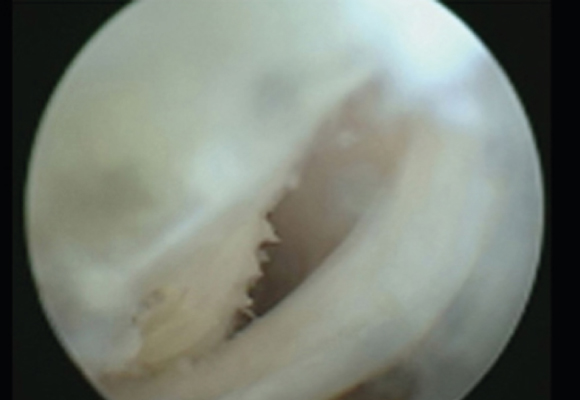

낭종 크기가 크고 통증이 심한 경우 무릎 뒤쪽의 혹을 제거하는 수술 시행

ㆍ환자 동의를 받은 자료이며, 이미지 사진은 실물과 다를 수 있습니다. (20.12.03)